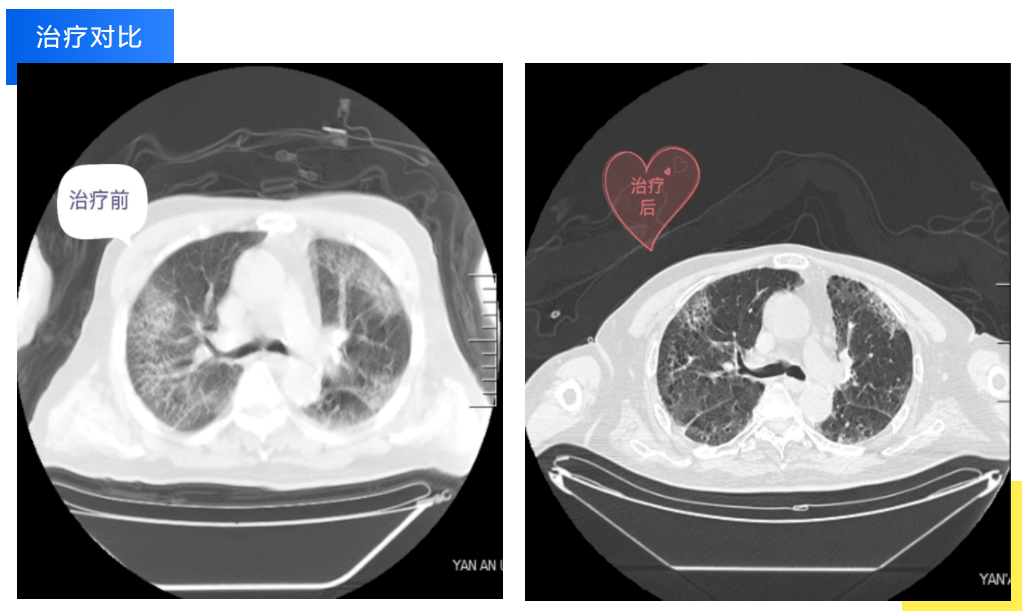

經過數日的治療和精心護理,老人呼吸衰竭的指標較前有了明顯的改善,氧合指數也從一開始的小于100mmHg逐漸提升到300mmHg以上,老人也感受到了醫護人員的良苦用心,從開始的抗拒到逐漸主動配合診療工作,目前已順利轉入下級醫院繼續康復。